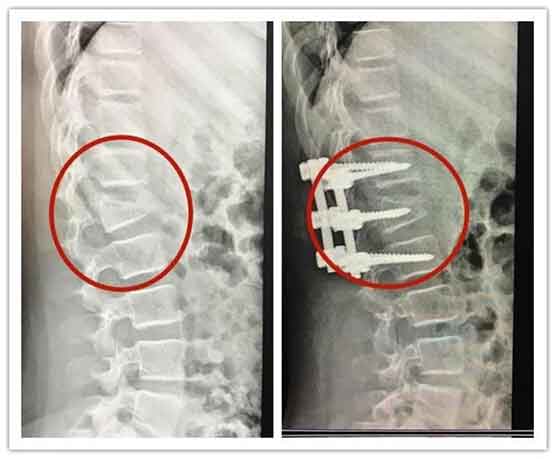

摔倒后,女孩当即痛苦倒地,双下肢迅速失去知觉,无法动弹。救护车抵达后,她被火速送往三甲医院抢救。经CT及核磁共振检查,诊断为腰椎爆裂性骨折,骨折碎片突入椎管,压迫脊髓神经。医生明确表示,若恢复不佳,可能面临终身瘫痪、双下肢功能受损、大小便失禁的高风险。

医学上,腰椎爆裂骨折指椎体受垂直压缩暴力碎裂成多块,骨折碎片向四周移位,尤其是向后突入椎管,像利刃般切断或压迫脊髓、马尾神经。L2-L4椎体骨质较薄,是最易发生爆裂骨折的部位。

目前,女孩已接受紧急减压内固定手术。医生强调,术后72小时是神经功能恢复的黄金窗口。若神经受压超过72小时,损伤将不可逆,瘫痪风险大幅上升。

治疗原则: 手术治疗:椎管减压+骨折复位内固定,解除神经压迫 康复周期:术后需长期康复,恢复时间长达6-12个月 护理要点:严格卧床、佩戴支具、避免腰部负重